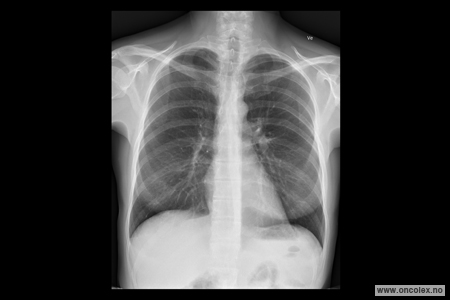

Røntgen toraks er en røntgenundersøkelse som tas for å se på lunger, hjerte og lymfeknuter i brystskilleveggen mellom lungene.

Under bildeopptaket står pasienten i en bestemt stilling foran røntgenapparatet.

Det tas bilder i front og fra siden.

Strålene som passerer gjennom kroppen treffer en sensor på den andre siden.

Røntgenbildet viser skjelett og lunger tydelig.